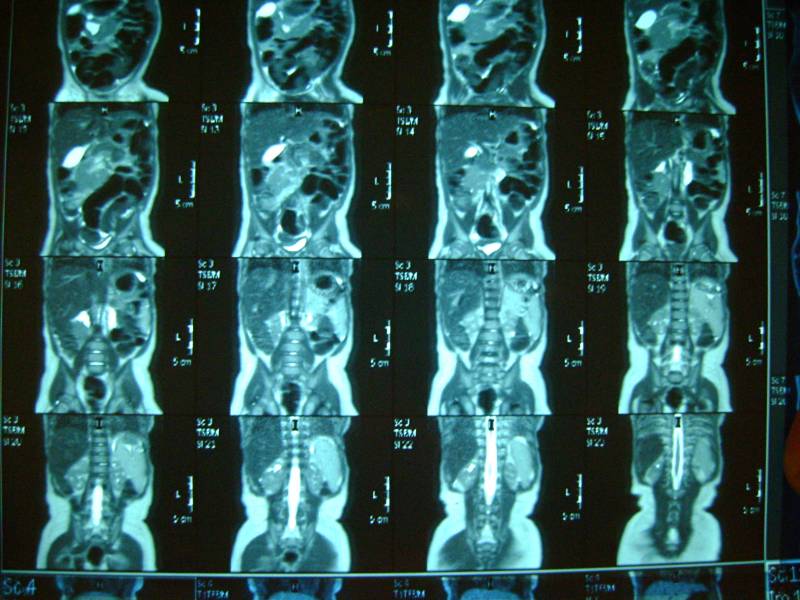

еще